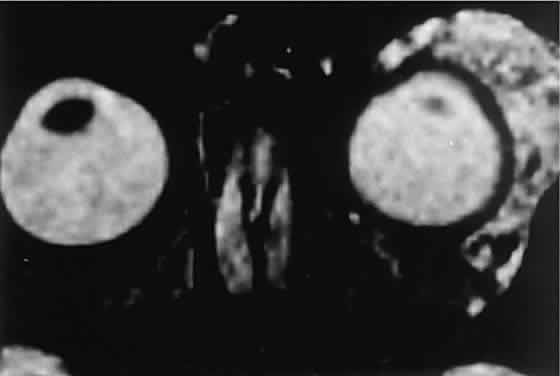

The high contrast sensitivity of MRI allows better delineation of capillary hemangioma from normal structures than does CT. The tumor is hyperintense in T2-weighted images with gadolinium and fat suppression (Fig. 8). Low-intensity streaks represent flow voids within higher flow draining and feeding vessels.

Fig. 8. Gadolinium-enhanced, fat-suppressed, T2-weighted MRI shows the extent of a large capillary hemangioma that infiltrates the lacrimal gland. Dark streaks represent flow voids within feeding and draining vessels.

CT discloses a single or multilobulated mass, which represents only the blood cyst portion of the tumor (Fig. 14). Individual lobules may have different radiodensities depending on the presence of clots or liquefied blood within each cyst (Fig. 15). A generalized increase in orbital dimensions suggests a long-standing, probably congenital process. Echography may help differentiate the cystic components of lymphangioma from cellular rhabdomyosarcoma. Echography shows the blood cysts to be acoustically inactive spaces, with extremely low internal reflectivity (Fig. 16). Clots within the cysts can increase internal heterogeneity, however. MRI has virtually eliminated the need for diagnostic biopsy in this condition, because of its ability to show differing magnetic properties of suspended, degrading blood products (Fig. 17).

Fig. 17. MRI scan of a 17-year-old girl with abrupt-onset proptosis. Multilobulated cystic spaces with fluid-fluid levels suggest recent hemorrhage within a previously unrecognized lymphangi-oma.